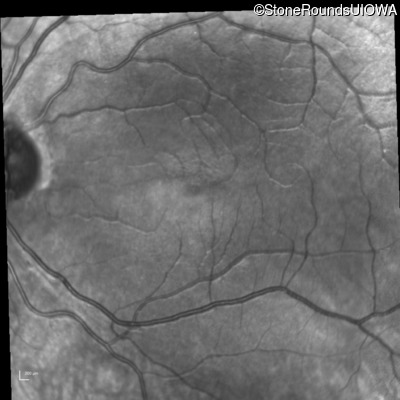

Age at visit: 17 years

This 17 year old male had normal vision until about 6 months earlier when he began to lose central vision. The left eye may have been affected prior to the right eye.

Leber Hereditary Optic Neuropathy MT-ND4 11778 A>G   MT